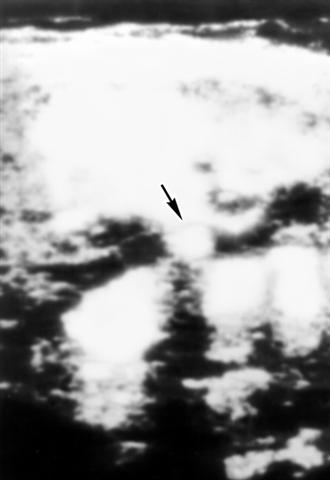

Рис. 1. Ультразвуковая сканограмма желчных путей при желчнокаменной болезни: стрелкой указан участок повышенной эхогенности, соответствующий камню общего желчного протока; под ним определяется черного цвета «акустическая дорожка».